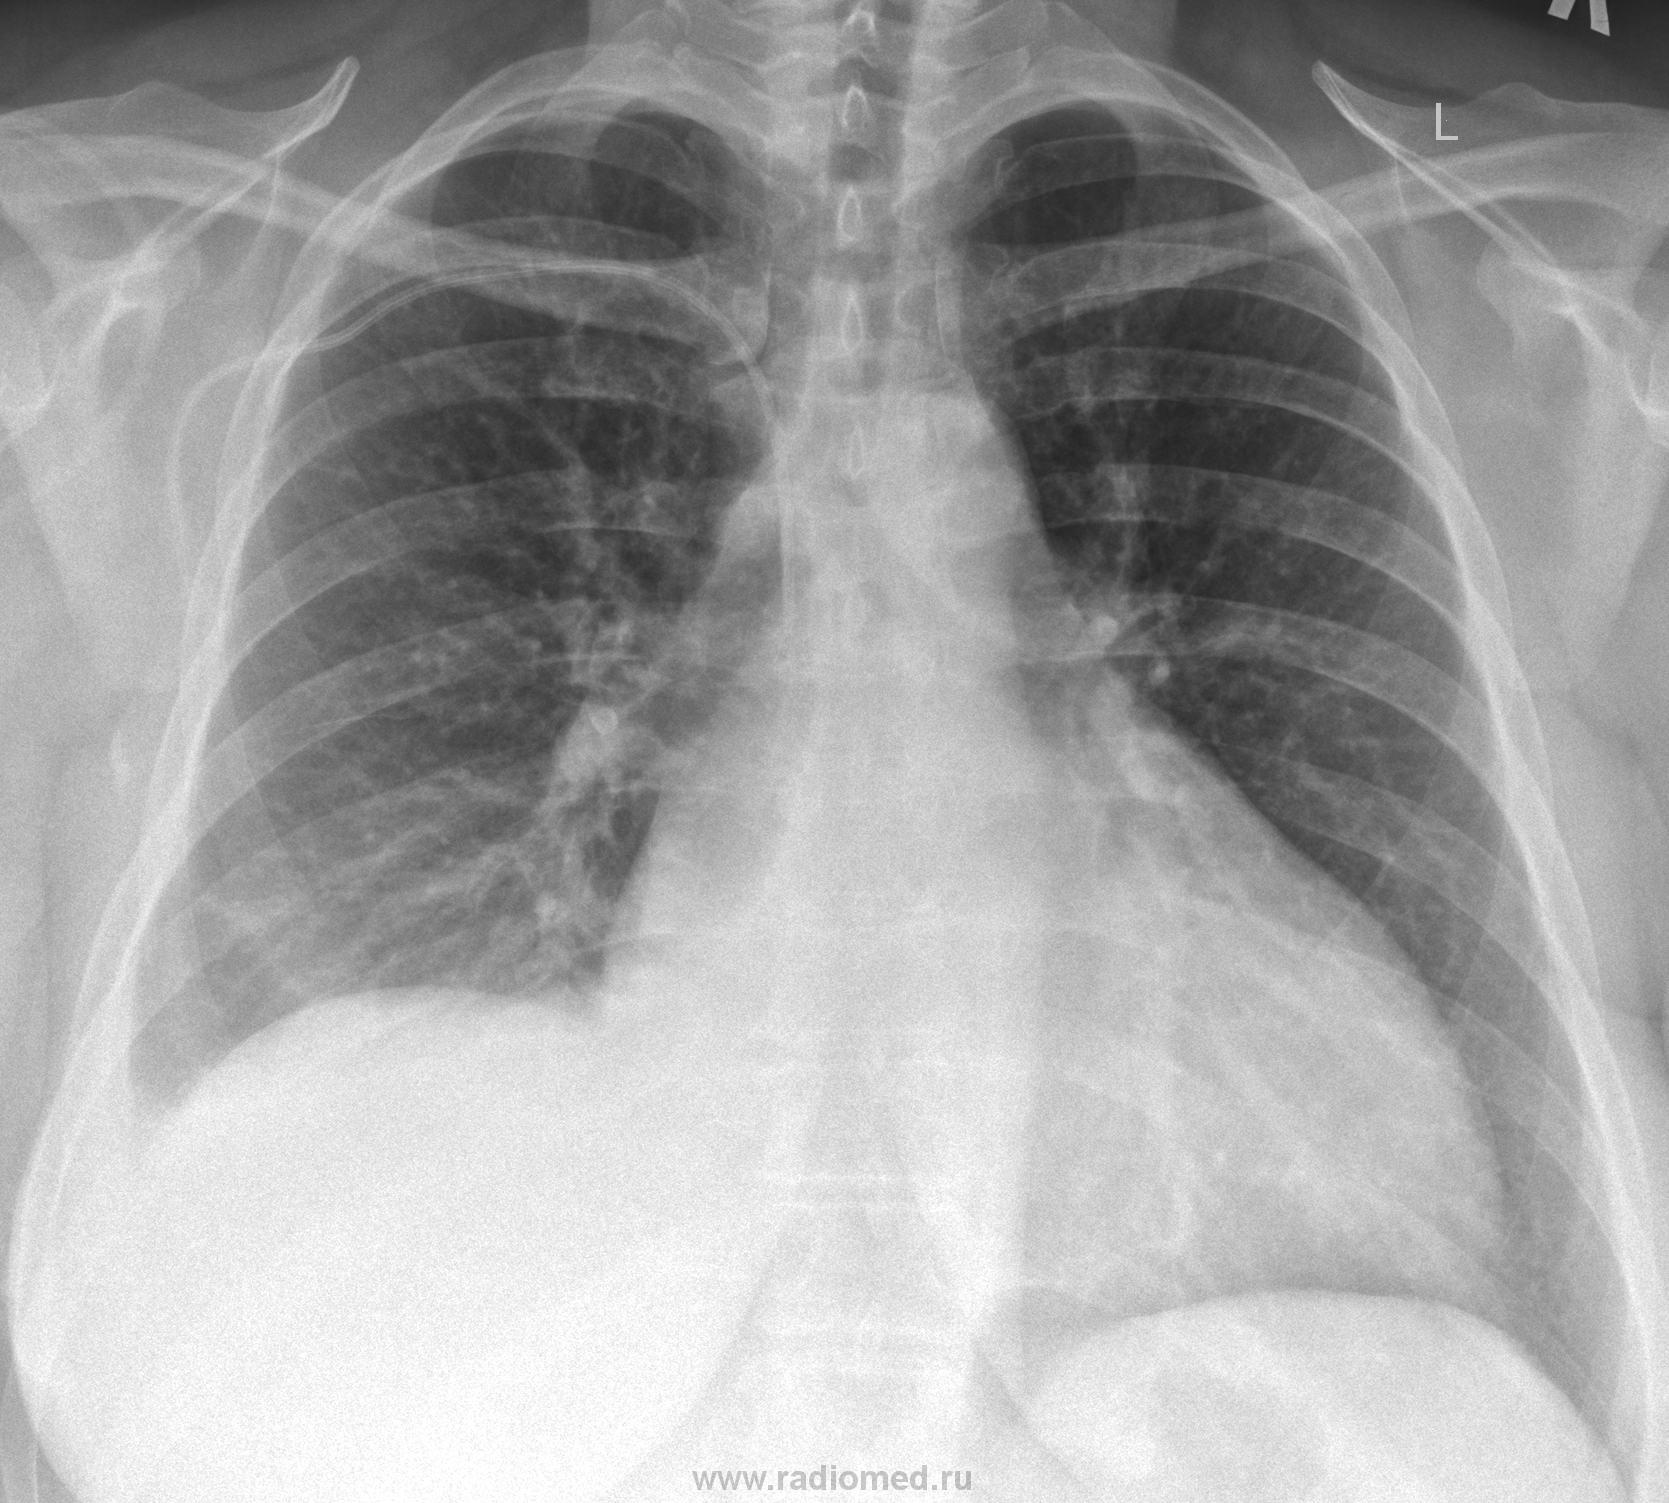

Валентин Львович это ещё ни всё, сегодня утром сделали контроль, динамика на лицо:

Изображение

А поповоду "классики" всё я как изночально предпологал так оно получилось по результатам МСКТ, а заключение сделал такое "ЗАКЛЮЧЕНИЕ:Оссумкованный паракостальный плеврит справа. Компрессионный ателектаз правого легкого. Связи раннее выполненной плевральной пункцией не искл. гемопневмоторакс справа."

Динамика динамикой, а в перикарде тоже жидкость?

А почему сердце такое большое?

Наталия, больная лежит в кардиохирургии...